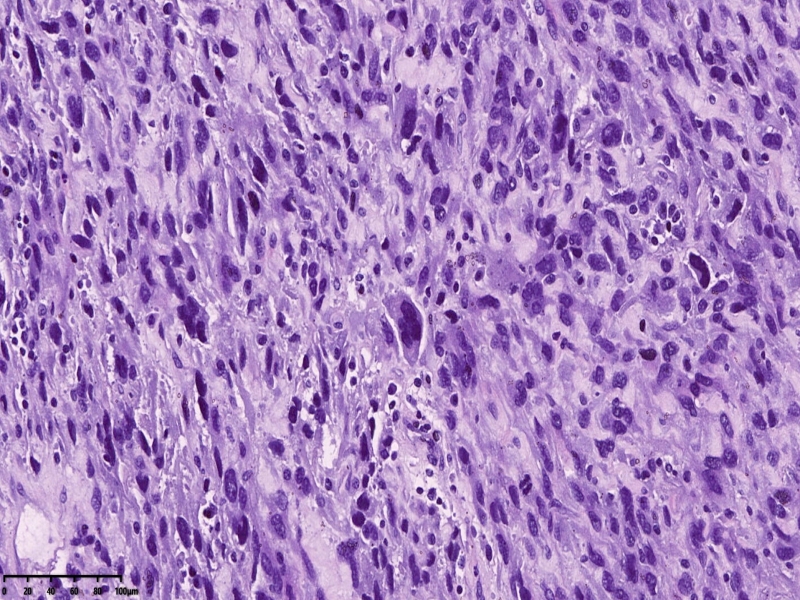

镜下可见肌间可见梭形瘤细胞,细胞核畸形,多核瘤巨细胞。坏死。